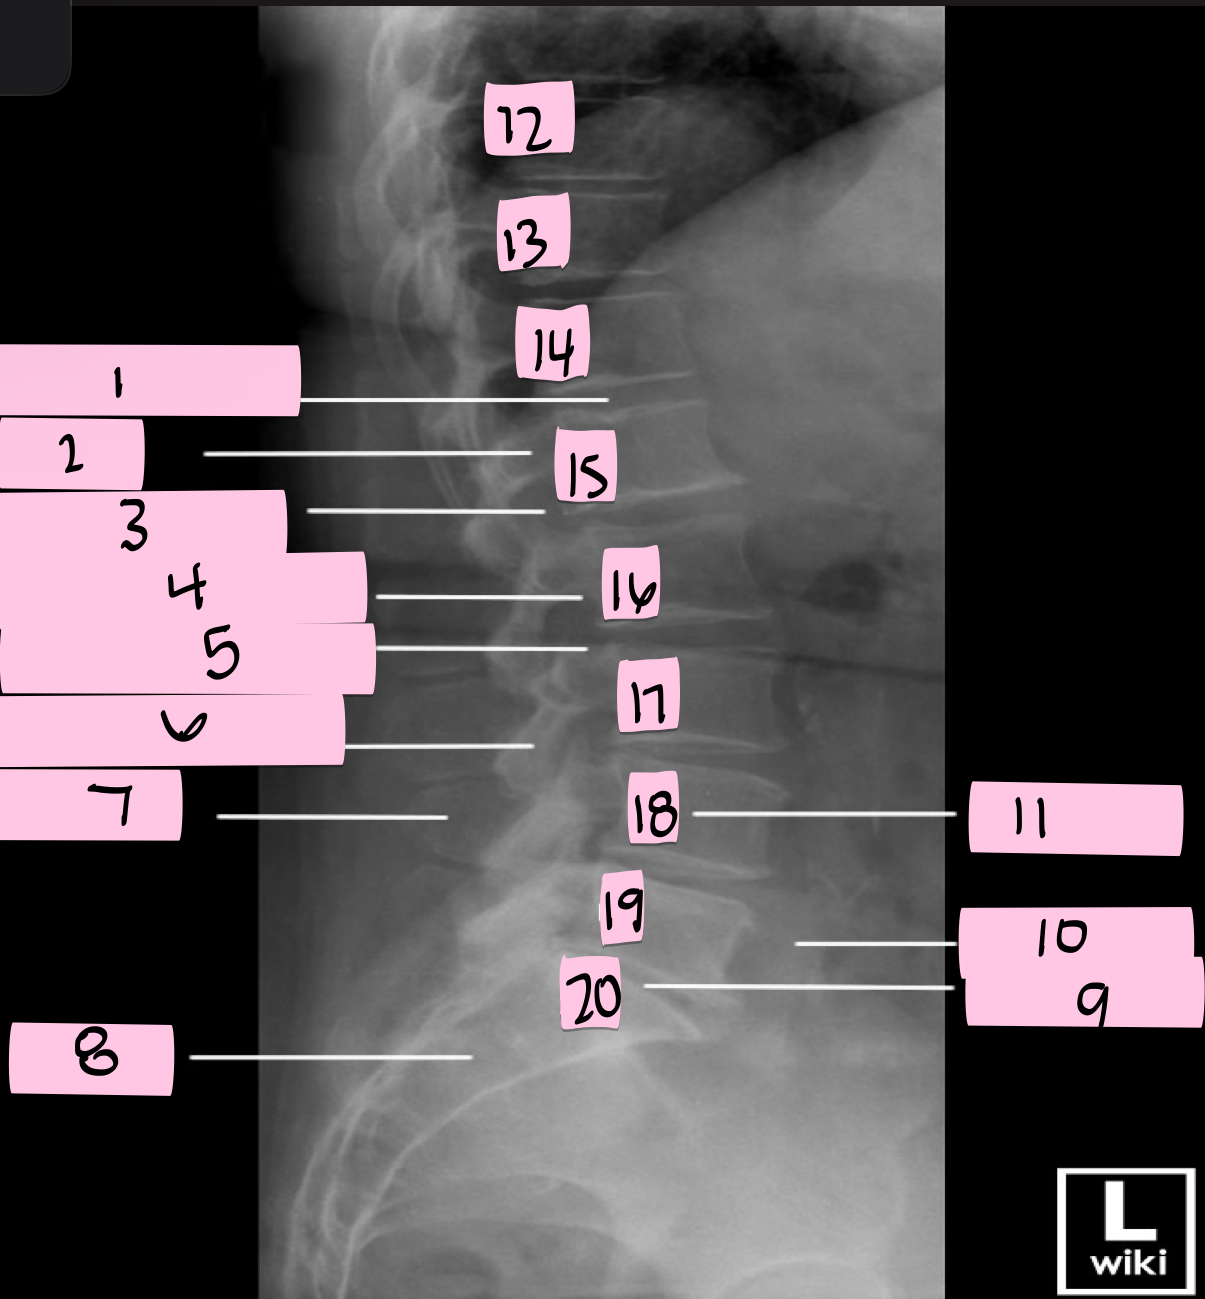

What is 1 pointing to?

Intervertebral disk

What is 2 pointing to?

Pedicle

What is 3 pointing to?

Intervertebral foramen

What is 4 pointing to?

Inferior vertebral notch

What is 5 pointing to?

Superior vertebral notch

What is 6 pointing to?

Inferior articular process

What is 7 pointing to?

Spinous process

What is 8 pointing to?

Sacrum

What is 9 pointing to?

L5 S1 joint

What is 10 pointing to?

Iliac crest

What is 11 pointing to?

Vertebral body (L4)

What is 12 pointing to?

T10

What is 13 pointing to?

T11

What is 14 pointing to?

T12

What is 15 pointing to?

L1

What is 16 pointing to?

L2

What is 17 pointing to?

L3

What is 18 pointing to?

L4

What is 19 pointing to?

L5

What is 20 pointing to?

S1